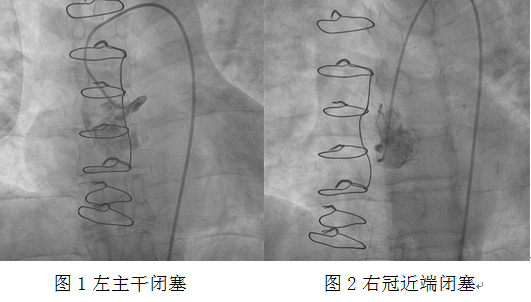

心血管介入團(tuán)隊(duì)立即予患者冠狀動(dòng)脈造影。造影顯示左主干閉塞、右冠狀動(dòng)脈近端閉塞。此時(shí)患者表情淡漠,血氧飽和度75%,為心源性休克狀態(tài)??紤]患者為橋血管急性閉塞,如不立即開通閉塞血管,患者有生命危險(xiǎn)!

介入團(tuán)隊(duì)經(jīng)過努力,發(fā)現(xiàn)前壁至右冠狀動(dòng)脈的靜脈橋血管急性閉塞,嘗試正向開通原血管困難,此時(shí)患者血氧飽和度進(jìn)一步下降,遂決定對急性閉塞的靜脈橋血管行急診介入治療。